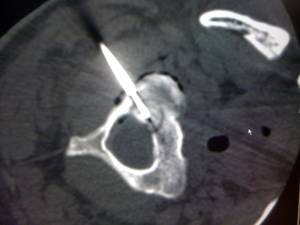

图3:射频电极置入 图4:取活检

术后无需制动即可活动,术后48小时出院,未服止痛药VAS评分0分。